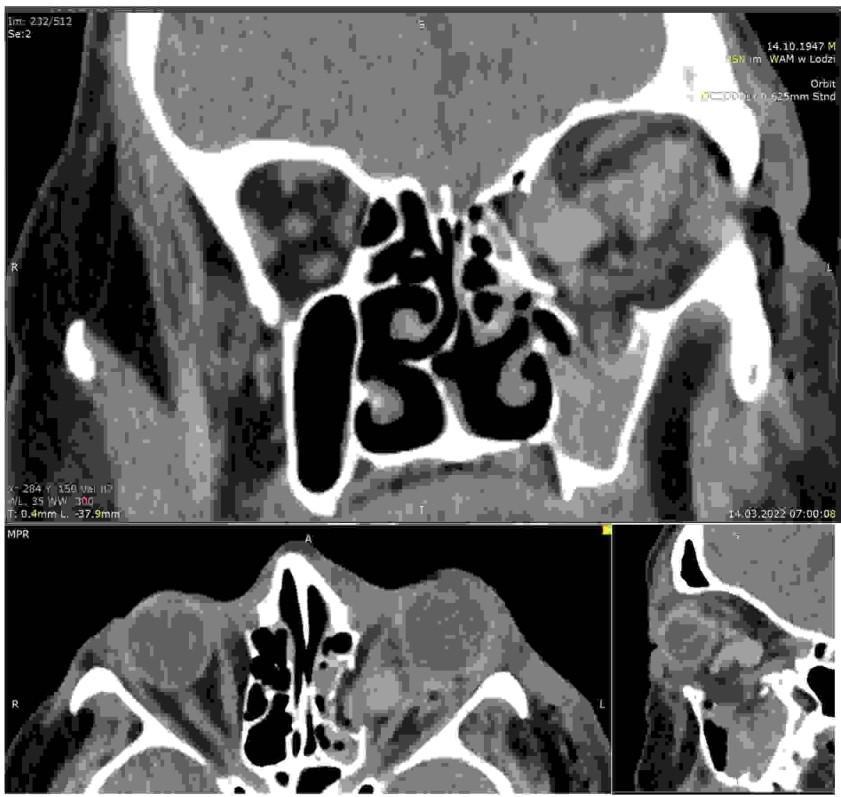

Pacjent (16 lat) uległ wypadkowi, jeżdżąc na hulajnodze. Doznał urazu okolicy bródkowej, gdzie ma ranę oraz urazu prawego policzka: zgryz otwarty całkowity od chwili urazu. Rozchwiany siekacz boczny dolny. Stan ogólny dobry: nie ma innych obrażeń ciała. Poniżej są obrazy z tomografii komputerowej wiązki wachlarzowej (FBCT). Wskaż prawidłowe leczenie:

Pytanie 76

Pacjentka (41 lat) została przywieziona po wypadku komunikacyjnym do SOR. Doznała izolowanego urazu żuchwy. Ma łuki zębowe. Stan ogólny dobry. Na poniższym przekroju wieńcowym otrzymanym ze spiralnej tomografii komputerowej zaznaczone są kąty przemieszczenia w złamaniach podstawy wyrostków kłykciowych żuchwy. Wskaż prawidłową metodę leczenia:

Pytanie 78